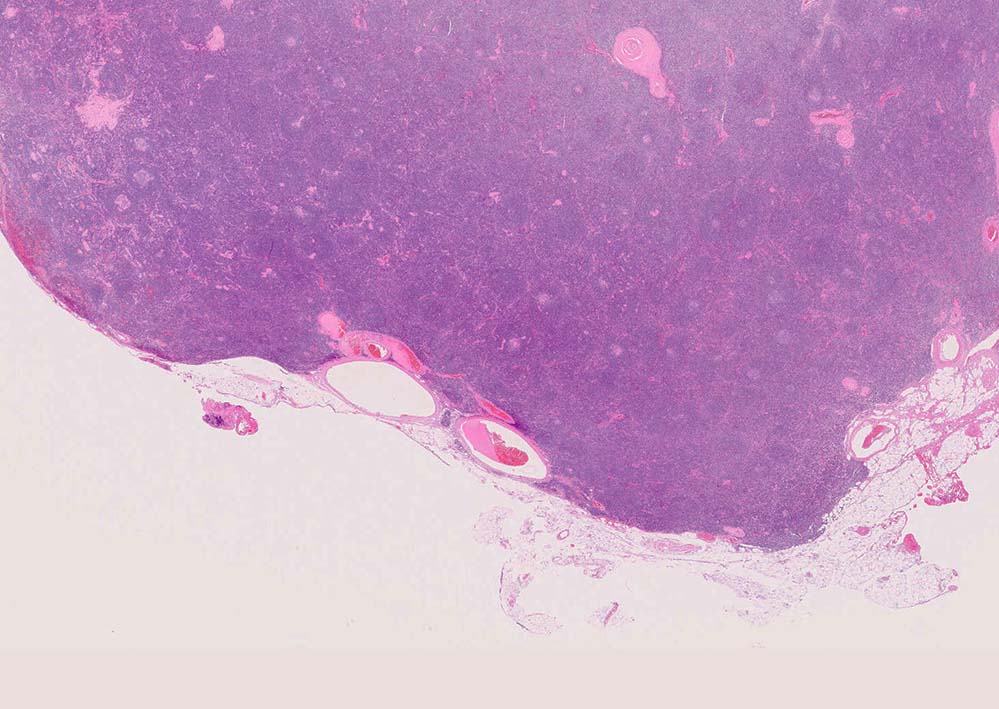

follicle03.jpg

硝子血管型 hyaline vascular type: 臨床症状に関係なく3つの病理組織所見で診断が決まる。*1

1. 萎縮した胚中心をもつ異常な血管増生を示すリンパ濾胞(Lolli-pop follicles. Lolli-popはキャンディ-の名前のようです)

2. 濾胞間リンパ組織の線維化, 血管増生

3. 被膜は肥厚し, 少なくとも病変中心部ではsinuses(リンパ洞)を欠いている

「広いmantle zoneの取り巻いたリンパ球の少ないFDCのめだつ小さな濾胞, 硝子化することもある, 濾胞間は細血管でいっぱい」がkey word